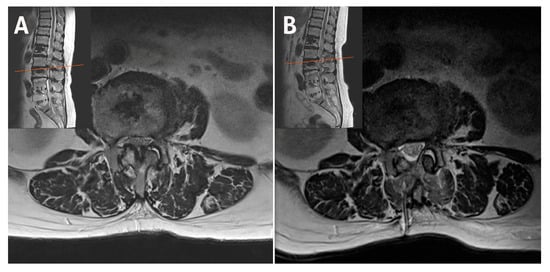

2.1. Case 1: Bilateral–Contralateral Decompression in Upper Lumbar Stenosis